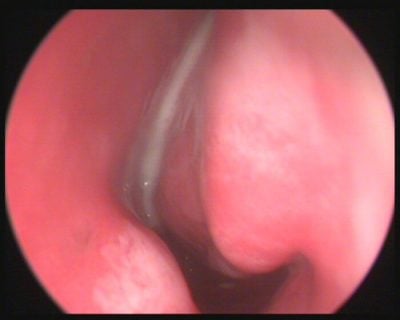

“Büyük geniz eti”, ebeveynlerin sıkça duyduğu ve çocukları için endişelenmelerine yol açan bir durumdur. ...

Geçmeyen ya da 10 gün ile 2 hafta arası süren Nezle Grip durumunda ...